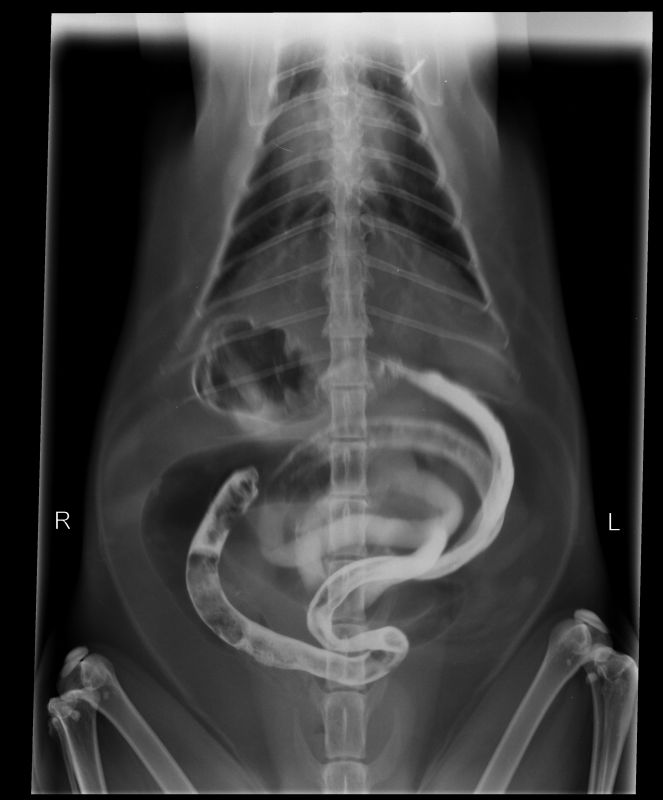

Abnormal Pathology on your pet

Shown on x-ray images which we have taken over the years.

Some interesting patient cases